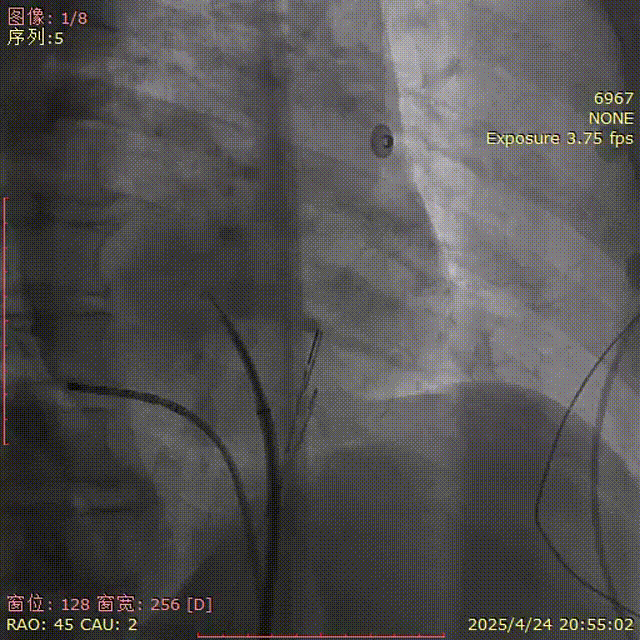

DSA下:造影剂显示已过房间隔

肝位造影

LAO 30° CAU 20°